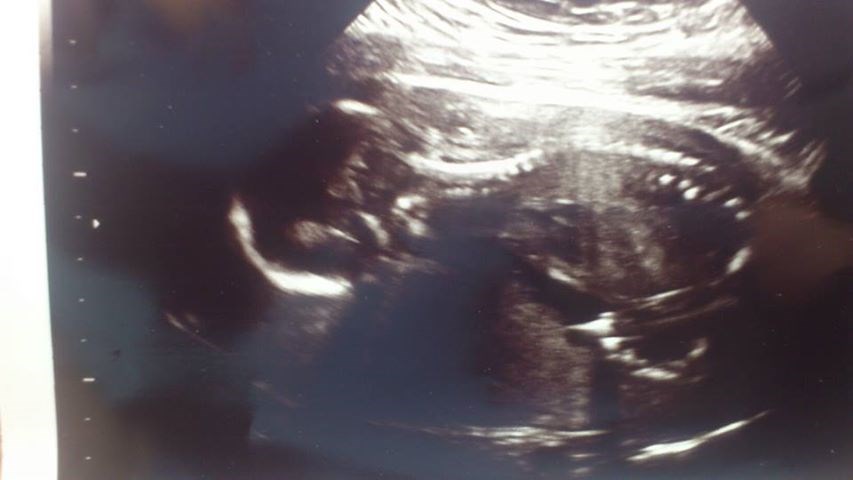

Knægten har simpelthen valgt at ligge på maven med benene godt op under sig, hænderne foran ansigtet og hovedet godt begravet i min moderkage og med ryggen ud mod min mave. Så der var ikke noget profil billede til mig, ej heller et billede hvor vi rigtig kunne se ham, men en ting er dog helt klart - han har en flot rygrad

Resultatet er dog rigtig godt, han fejler ingenting den lille bandit, men pga. hans stædighed fik jeg hverken mål eller vægt på ham

Men hun mener at han er omkring 25 cm.